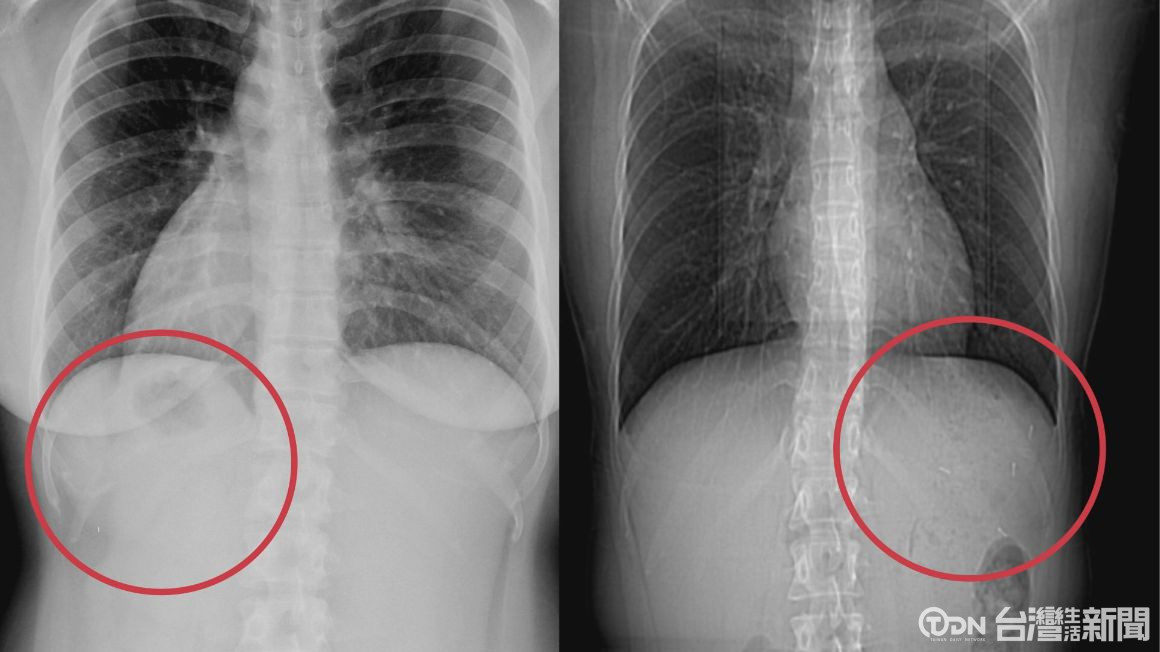

▲雙寶媽天生的臟器逆位,心肝脾肺腎及胃腸道等,都和正常人器官左右相反/記者 李晉仰攝

▲臟器逆位挑戰胃縮手術成為全球第二例/記者 李晉仰攝